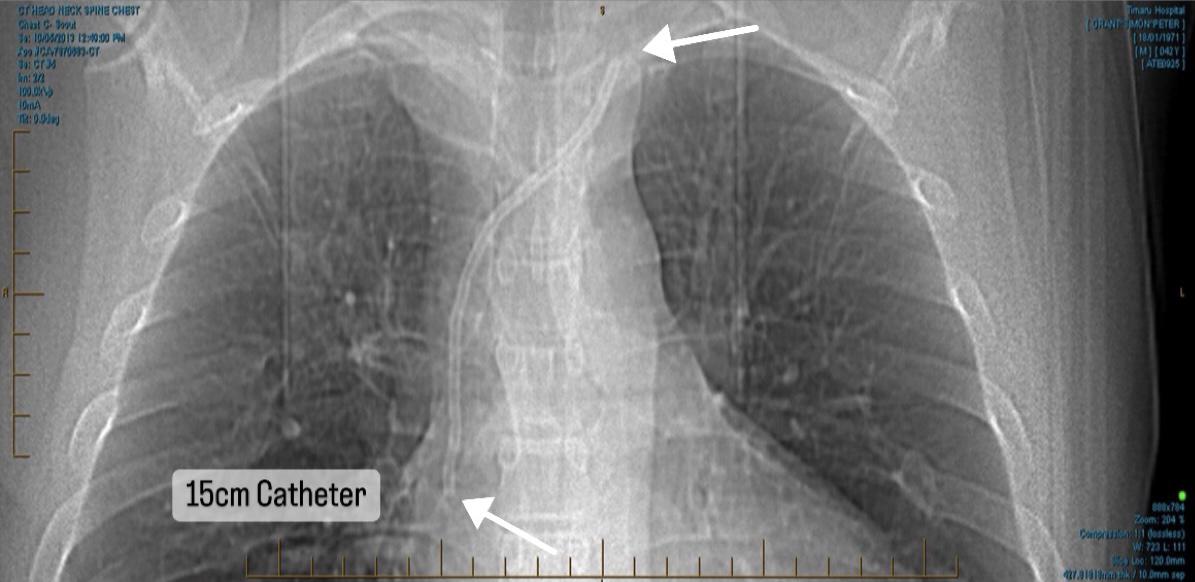

15CM PIECE OF PLASTIC LEFT IN TOP OF HEART – SURGERY NOT AVAILABLE IN NZ

After going through lengthy consultations with cardiologists throughout Australasia, it has been formally confirmed there are no options for removal with no expertise available for this complex treatment injury. The US remains the focal point. Without removal, future dialysis and transplant options are not feasible. We thank everyone for their ongoing support and generosity.

Main image

We are hopeful of finding a surgeon in Melbourne that can apply the same laser sheath removal technique. Going to the US currently is not feasible due to rising costs of surgery and the exchange rate both being cost prohibitive. The average cardiothoracic procedure in Australia is around $70,000 (for an extraction of pacemaker leads), so we are hopeful a surgeon can apply the same principal with an embedded fractured catheter. The major hurdle is the length of time the catheter has remained in situ and the fact they don't do these procedures routinely as it should never happen, hence being in this unique situation. The only way of getting to the US now will be if ACC change their legislation to enable treatment injury cases to get the surgery they need if it's not available in NZ. Thankyou so much to everyone who has donated, we can't reiterate enough how appreciative we are. The attached image is a 3D image created by the surgeon from the US showing the catheter and fragments in bright green sitting in the SVC (superior vena cava) inside the heart.